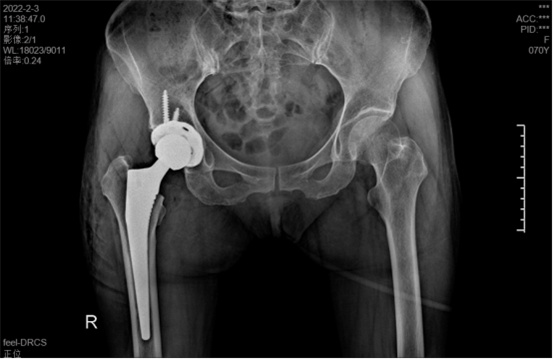

據(jù)羅軍主任介紹,他們首先將鄭阿姨的術(shù)前CT數(shù)據(jù)導(dǎo)入到系統(tǒng)中,通過自動識別骨盆和股骨建立了計(jì)算機(jī)數(shù)字三維模型。AI HIP顯示患者適合使用合適的髖臼杯、股骨柄、標(biāo)準(zhǔn)陶瓷球頭、陶瓷內(nèi)襯,并精準(zhǔn)定位了截骨線,有效幫助醫(yī)生在手術(shù)中做到精確截骨。

在完善相關(guān)檢查充分評估患者身體情況及手術(shù)風(fēng)險(xiǎn)后,羅軍主任改變傳統(tǒng)手術(shù)方式,在易觀俊主治醫(yī)師、柴重喜醫(yī)師等助手的配合下,為鄭阿姨實(shí)施了人工智能規(guī)劃輔助DAA入路全髖關(guān)節(jié)置換術(shù)。

術(shù)中假體植入和術(shù)前規(guī)劃完全一致

術(shù)中,醫(yī)生在患者髂前上棘外側(cè)切開約8cm長的切口,小心翼翼地利用闊筋膜張肌與縫匠肌之間的間隙露出髖關(guān)節(jié)。經(jīng)過一番精細(xì)、高難度的操作,成功植入人工髖關(guān)節(jié)組件,以取代受損的股骨頭和髖臼。由于手術(shù)切口小,肌肉組織未受損,鄭阿姨恢復(fù)很快,術(shù)后第1天就能下床活動。